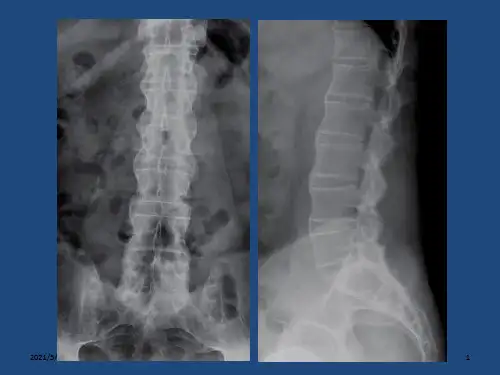

强直性脊柱炎 ppt课件